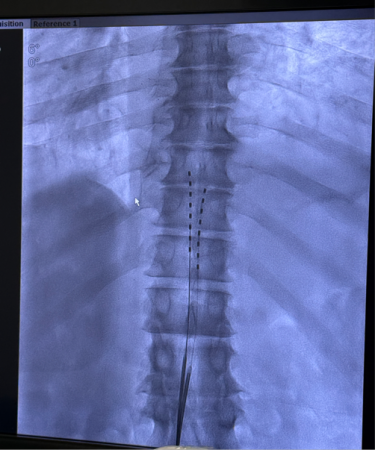

Electrode Successfully Implanted

The surgery was performed under DSA

(Digital Subtraction Angiography) guidance. Under the direction of Chief

Physician Xiao Hong, the surgical team, consisting of Nurse Yin Yan and

Research Assistant Lu Fan, precisely delivered the electrode to the corresponding

segment of the patient's epidural space and completed intraoperative

stimulation parameter adjustments. Mr. T immediately reported that the coverage

area of the electrical stimulation highly coincided with his pain region,

experiencing an immediate analgesic effect. The surgical procedure was

completed smoothly.